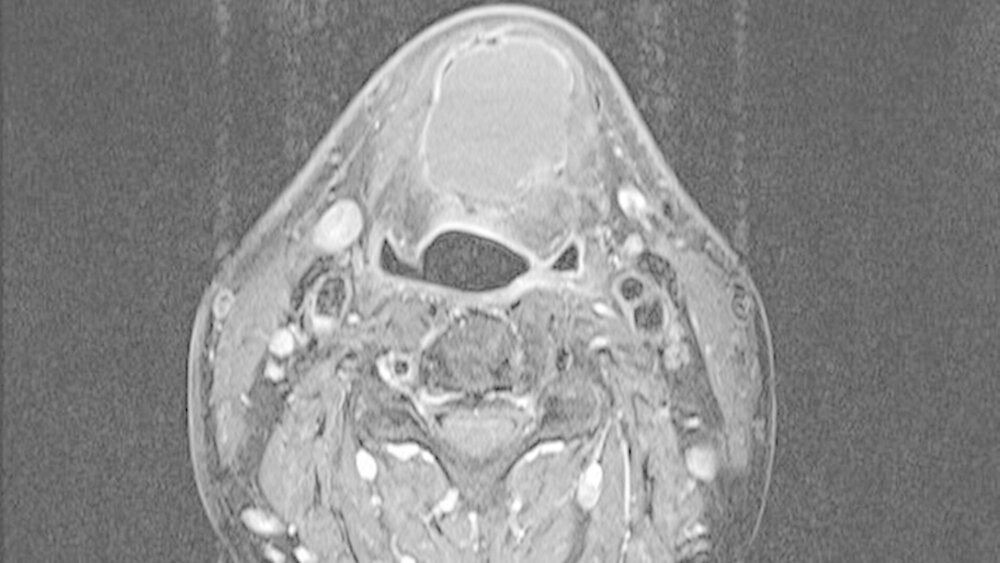

Die unter ambulanten Bedingungen angefertigte schnittbildgebende MRT-Untersuchung des Halses zeigte eine 41x35x27 mm große, gut abgrenzbare, und abgekapselte Raumforderung mit homogener Binnenstruktur. Die Dichtewertemessung wies anhand der Verteilung der Hounsfield-Einheiten einen mit flüssigkeits-äquivalentem, gefüllten Hohlraum auf (Abbildung 2a). Dieser war mit einer mittigen Einschnürung in der Medianebene des Halses und in der Mitte des Os hyoideum lokalisiert (Abbildung 2b). Dabei wird die Verdrängung des aerodigistiven, benachbarten Raumes sowie die Anhebung des Mundbodens und der Zungengrundmuskulatur deutlich (Abbildung 2c).